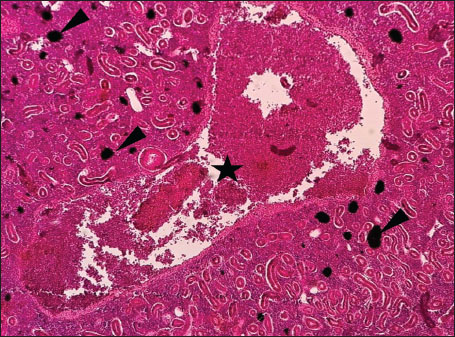

Histopathological examination of the kidney tissues of L. sceleratus revealed multiple alterations. Prominent melanomacrophage centers (MMCs), necrotic areas, dilatation of Bowman’s capsules, and vacuolar degeneration were observed (Fig. 1), associated with interstitial lymphohematopoietic tissue (Fig. 2). Dilated and congested blood vessels and extensive MMCs were also noted (Fig. 3). Renal degeneration surrounding lymphohematopoietic tissue, large clusters of MMCs, and thickened, congested vessel walls within fibrotic areas were evident (Fig. 4). Atrophic renal degeneration with necrotic and vacuolar changes was observed (Fig. 5). Severe inflammatory infiltration of lymphatic cells and granulomas with necrotic centers, surrounded by fibrous tissue, was detected (Figs. 67).

Fig. 2. Histopathology of the kidney in an adult L. sceleratus showing renal degeneration with necrotic areas (stars), severe MMCs (head arrows), and interstitial lymphohematopoietic tissue (thick arrows). ×40 H&E.

The present study revealed pronounced histopathological alterations in both the kidneys and gills of L. sceleratus collected along the Libyan coast. Kidney lesions, including tubular degeneration, Bowman’s capsule dilatation, proliferation of MMCs, vascular congestion, and inflammatory infiltration, were associated with histologically detected structures, but no parasitic structures were detected in kidney tissues. These patterns are commonly reported in marine teleosts exposed to chronic environmental stressors (Ali et al., 2014; Steinel and Bolnick, 2017; Carreras-Colom et al., 2022). These lesions should be interpreted as descriptive indicators of physiological stress rather than direct evidence of chemical pollution or causality, consistent with Flores-Lopes and Thomaz (2011). Vascular abnormalities, including congestion and thickened vessel walls, were evident, which may reflect chronic circulatory disturbances or inflammatory responses rather than acute toxicity (Bernet et al., 1999; Thophon et al., 2003). Interstitial lymphohematopoietic tissue, inflammatory cell infiltration, and granulomatous formations suggest that parasitic or microbial challenges could contribute to renal lesions. Despite these histopathological changes, the sampled fish appeared healthy at capture, demonstrating the potential physiological resilience of marine teleosts. Fish kidneys possess compensatory mechanisms, and gills serve critical osmoregulatory and excretory functions, allowing survival despite structural alterations (Evans et al., 2005; Hwang et al., 2011; Hinton et al., 2018; Leone et al., 2018). Gradual development of renal lesions likely enables adaptation without acute organ failure.